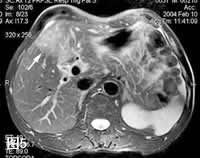

图5: MRI、T2WI,肿瘤呈相对高信号(箭号)。, http://www.100md.com